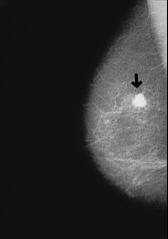

Example: x-ray photo of a pneumonia with shadowed medium and upper part of the lung (right).

-- pneumonia, x-ray photo: http://www.doktor.ch/krankheiten/lungenentzuendung.html